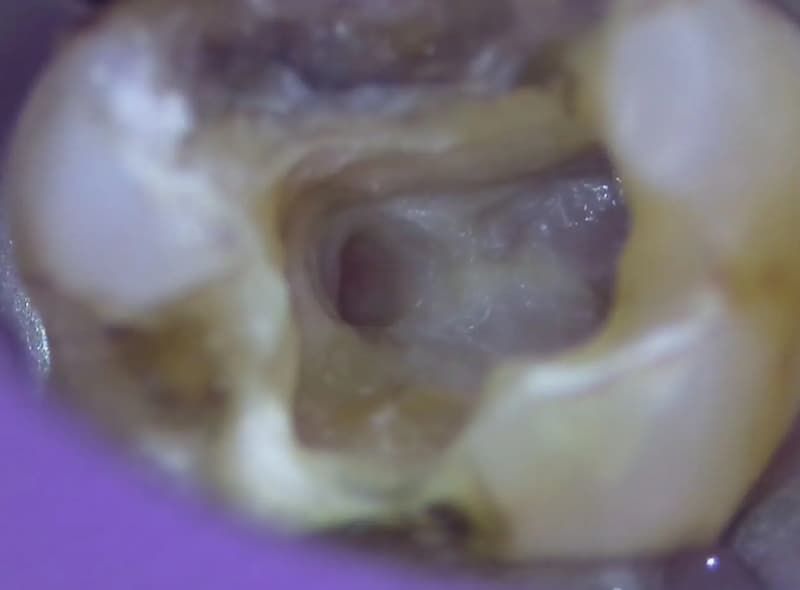

当クリニックでは根菅治療を行う際、「マイクロスコープ」という機器を使用しております。これまで肉眼では見えなかった根管の中を目でみて確認できるので、より丁寧で正確な治療が可能です。何もしなくても歯がズキズキと痛む方、食べ物を噛んだ時に痛みや違和感を覚える方は是非ご相談ください。

実際にマイクロスコープから

みた視野

根管治療(根の治療)は歯の内部の細かい管を綺麗に掃除していく治療です。肉眼ではほとんど見えない複雑な構造を持つ部位ですが、このようにマイクロスコープを通して治療すると、根の内部の状態を確認しながら作業することができます。菌に侵された部分を丁寧に取り除き、お薬を詰めることが可能です。